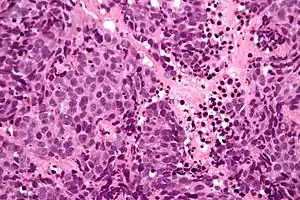

| Micrograph of a SNUC. H&E stain. | |

Low mag.

High mag.